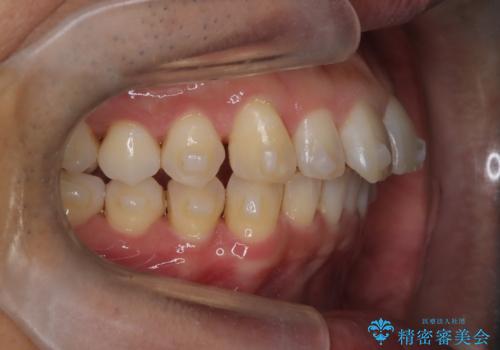

【インザライン】前歯の凸凹を治したい

- 前歯の凸凹を主訴に来院されました。

下顎位が右方に変異しており、外科矯正も提案しましたが患者様は希望されず、インビザラインにて治療を完了しております。

叢生のスペースを確保するために、臼歯部の遠心移動を行っています。

今回の治療計画は上顎の正中を顔と揃えることを優先しています。